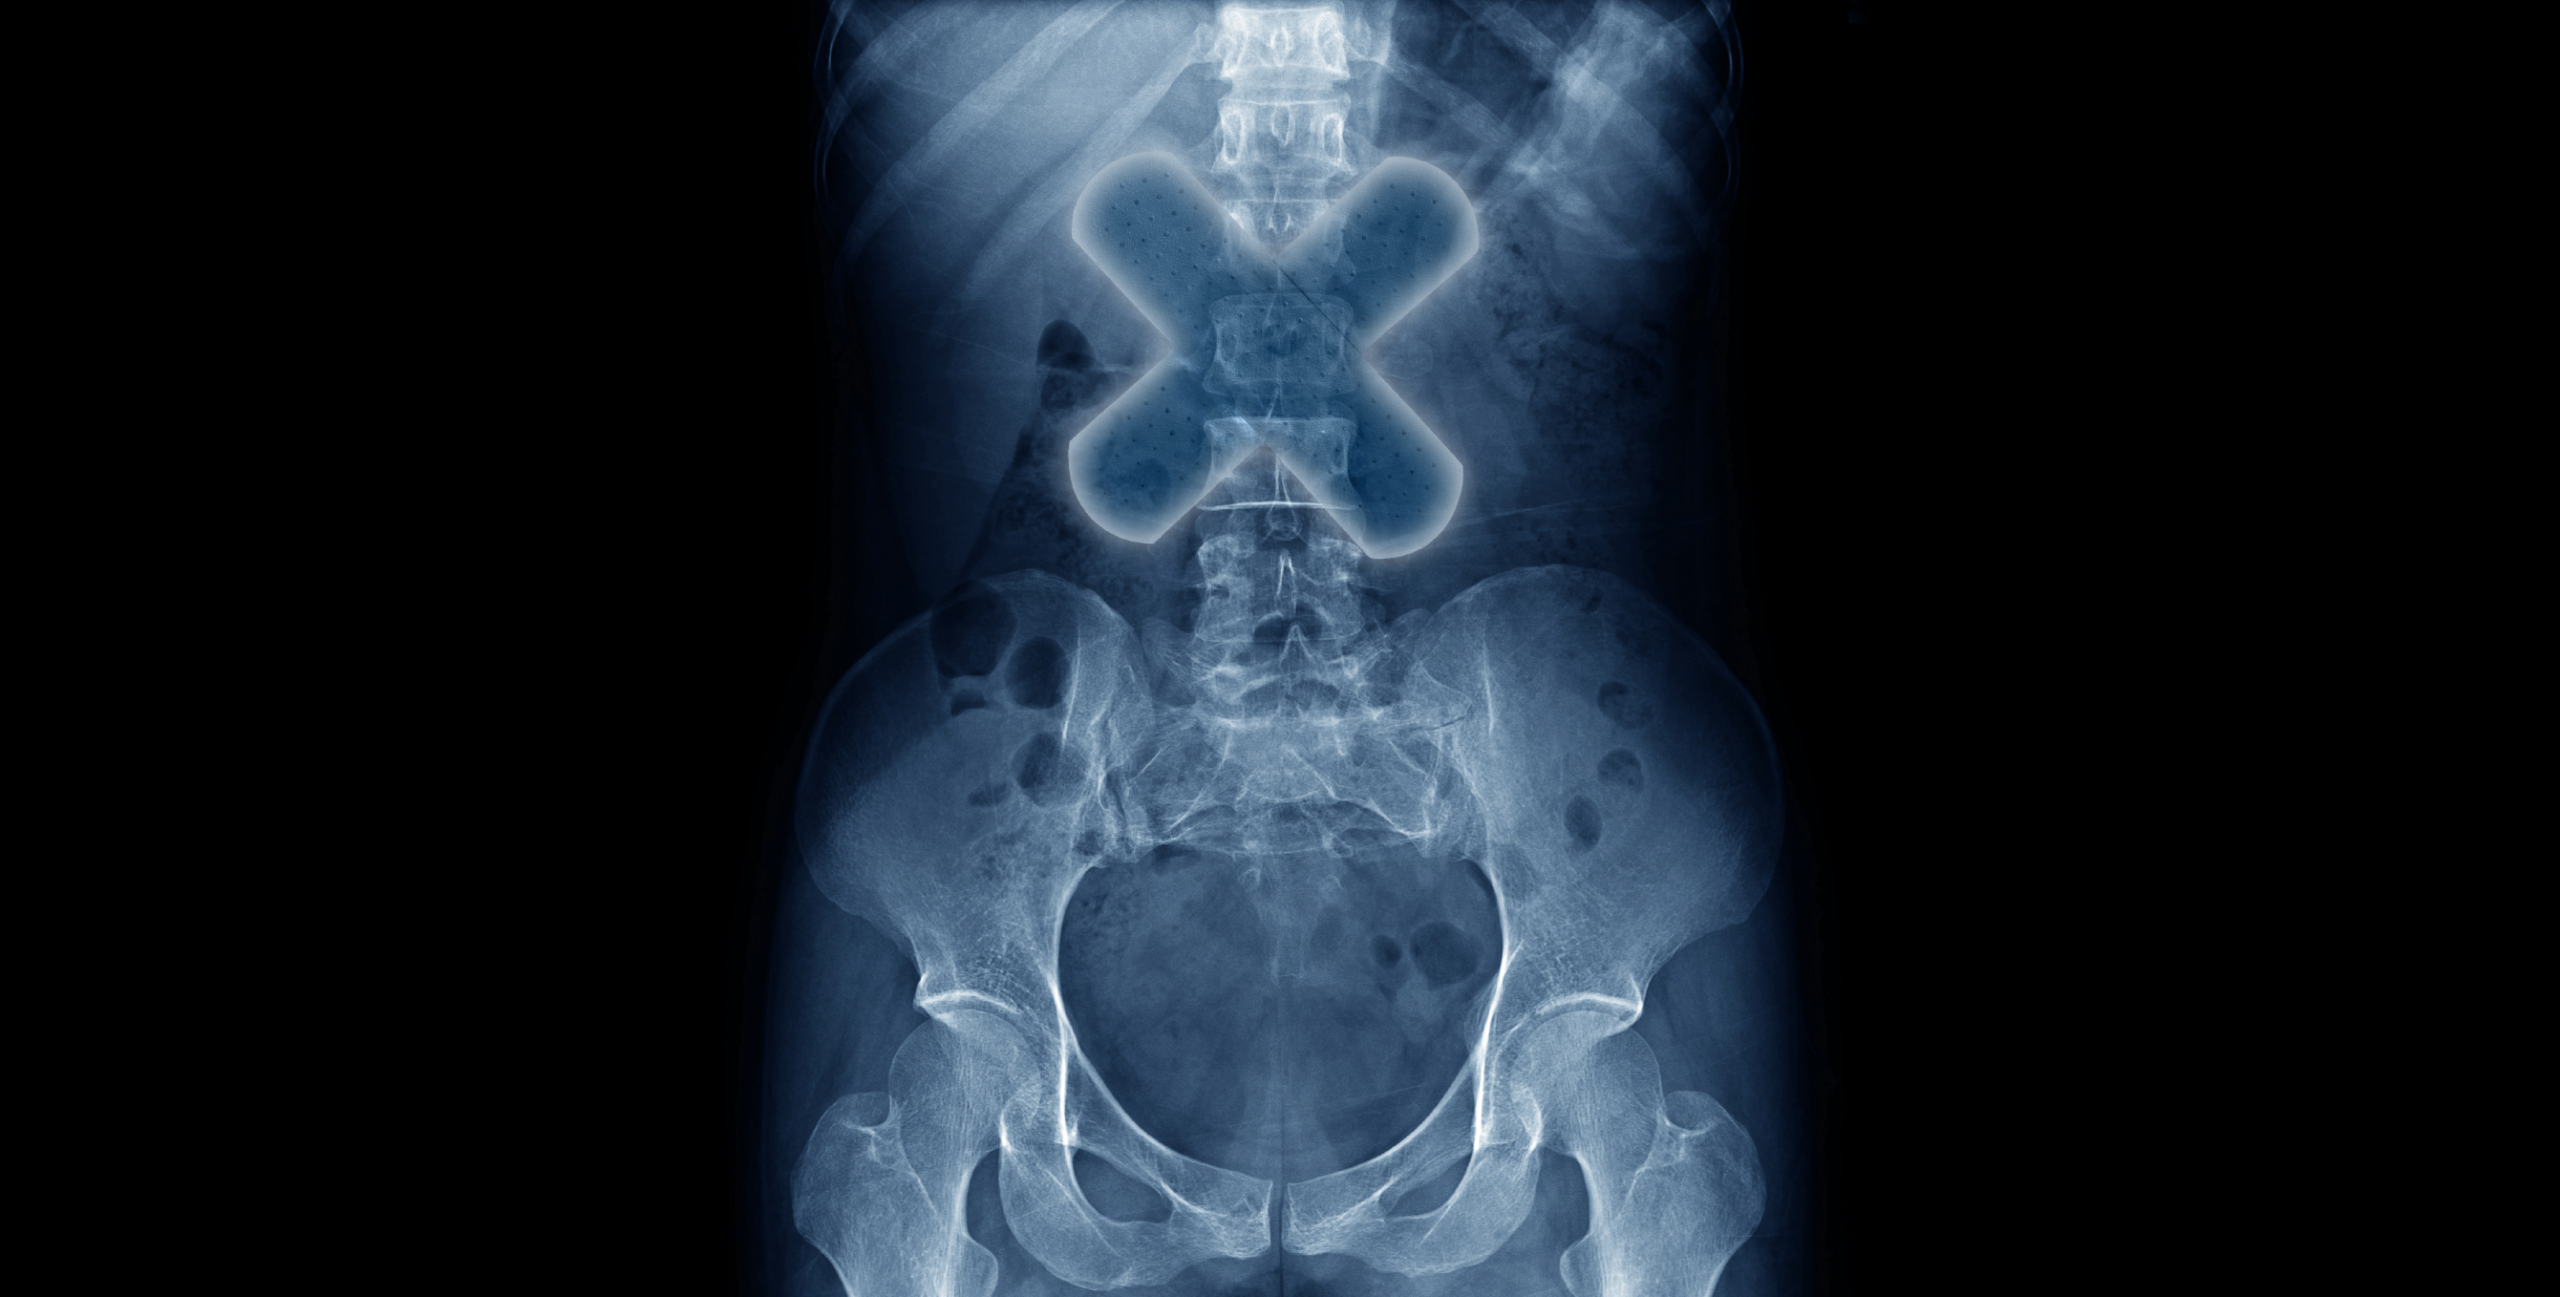

A Justiça Federal em Minas Gerais autorizou, em caráter excepcional, o uso compassivo do medicamento experimental Polilaminina em um paciente com lesão medular completa, após reconhecer a gravidade extrema do quadro clínico e a inexistência de alternativas terapêuticas eficazes no tratamento convencional. O medicamento ainda está em desenvolvimento clínico. O uso compassivo da Polilaminina foi apontado como a única intervenção potencialmente apta a modificar curso da lesão, ainda que sem garantia de eficácia. A decisão foi proferida em 20 de janeiro de 2026 pelo juiz federal substituto Christian Lucas del Cantoni, da 4ª Vara Federal Cível e Juizado Especial Federal Adjunto de Belo Horizonte, da Seção Judiciária de Minas Gerais.

De acordo com a decisão, a documentação médica apresentada comprova que o paciente possui diagnóstico inequívoco de lesão medular completa, com prognóstico reservado e sem expectativa de recuperação neurológica por meio das terapias atualmente disponíveis.